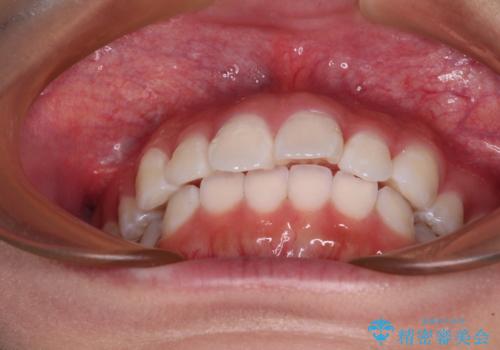

- 上下前歯の叢生を気にして来院された患者様です。

インビザラインでの治療を希望されていて、デコボコの程度が中等度であり、安価なパッケージにて対応可能と判断されたため、インビザライン・モデレートを用いて矯正治療を行うこととしました。